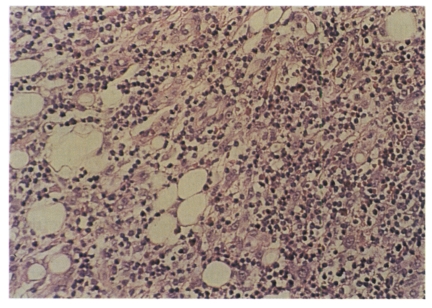

A 63-year-old male with a pruritic pea-sized brownish nodule in the left popliteal area was referred to us in June 1999. Asymptomatic solitary nodule had been found in the left popliteal area about 20 days before admission. Then, the nodule was accompanied by pruritus, erythema, and pain. He was a farmer and frequently worked in the field. Past history and family history were nonspecific. On admission, the erythematous area was surmounted by a 5×7 mm sized arthropod which was firmly attached to the skin by the mouth part (Fig. 1). Laboratory studies were normal or negative. The tick and surrounding skin were removed intact by an excision biopsy, and submitted for histologic study. Histopathologic examination revealed dilated vessels and dense perivascular inflammatory infiltrates composed of lymphocytes and eosinophils in the dermis and subcutis (Fig. 2). After excision, the wound healed well and no recurrence happened.

Winer and Strakosch (1941) divided the histological findings of tick bite into three stages with reference to duration: acute (a month or less), subacute (several months), and chronic (a year or more) stage. In the acute stage, dilated blood vessels and perivascular inflammatory infilitrates composed of lymphocytes and eosinophils in the superficial dermis are observed. In the subacute stage, extensive perivascular inflammatory infilitrates composed of lymphocytes, neutrophils, fibroblasts, and eosinophils are prominent. In the chronic stage, fibrous tissue proliferation, a few Langhans' giant cells, lymphocytes, and eosinophils deposited between fibrous tissues are observed. In the case 1, histologic manifestations were dilated vessels and perivascular infiltrates of eosinophils and lymphocytes in the dermis and subcutis, indicating an acute stage of tick bite.